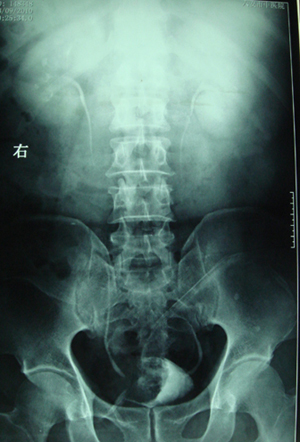

典型病例,男,56岁。无痛性血尿3月。

膀胱占位性病变,呈菜花状生长,考虑膀胱癌。 期待病理。